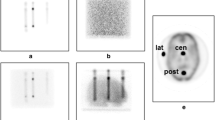

Iterative reconstruction techniques such as an ordered subsets-expectation maximization (OSEM) algorithm can easily incorporated various physical models of attenuation or scatter. We implemented OSEM reconstruction algorithm incorporating compensation for distance-dependent blurring due to the collimator in SPECT. The algorithm was examined by computer simulation to estimate the accuracy for brain perfusion study.Methods: The detector response was assumed to be a two-dimensional Gauss function and the width of the function varied linearly with the source-to-detector distance. The attenuation compensation (AC) was also included. To investigate the properties of the algorithm, we performed computer simulations with the point source and digital brain phantoms. In the point source phantom, the uniformity of FWHM for the radial, tangential and longitudinal directions was evaluated on the reconstruction image. As for the brain phantom, quantitative accuracy was estimated by comparing the reconstructed images with the true image by the mean square error (MSE) and the ratio of gray and white matter counts (G/W). Both noise free and noisy simulations were examined.Results: In the point source simulation, FWHM in radial, tangential and longitudinal directions were 14.7, 14.7 and 15.0 mm at the image center and were 15.9, 9.83 and 10.6 mm at a distance of 15 cm from the center by using FBP, respectively. On the other hand, they were 8.12, 8.12 and 7.83 mm at the image center, and were 7.45, 7.44 and 7.01mm at 15 cm from the center by OSEM with distance-dependent resolution compensation (DRC). An isotropic and stationary resolution was obtained at any location by OSEM with DRC. The spatial resolution was also improved about 6.5 mm by OSEM with DRC at the image center. In the brain phantom simulation, the blurring at the edge of the brain structure was eliminated by using OSEM with both DRC and AC. The G/W was 2.95 and 2.68 for noise free and noisy cases, respectively, when no compensation was performed. But the values for G/W without and with noise became 3.45 and 3.21 with AC only and were improved to 3.75 and 3.71 with both AC and DRC. The G/W approached the true value (4.00) by using OSEM with both AC and DRC even when there was statistical noise.Conclusion: In conclusion, OSEM reconstruction including the distance-dependent resolution compensation algorithm was reasonably successful in achieving isotropic and stationary resolution and improving the quantitative accuracy for brain perfusion SPECT.